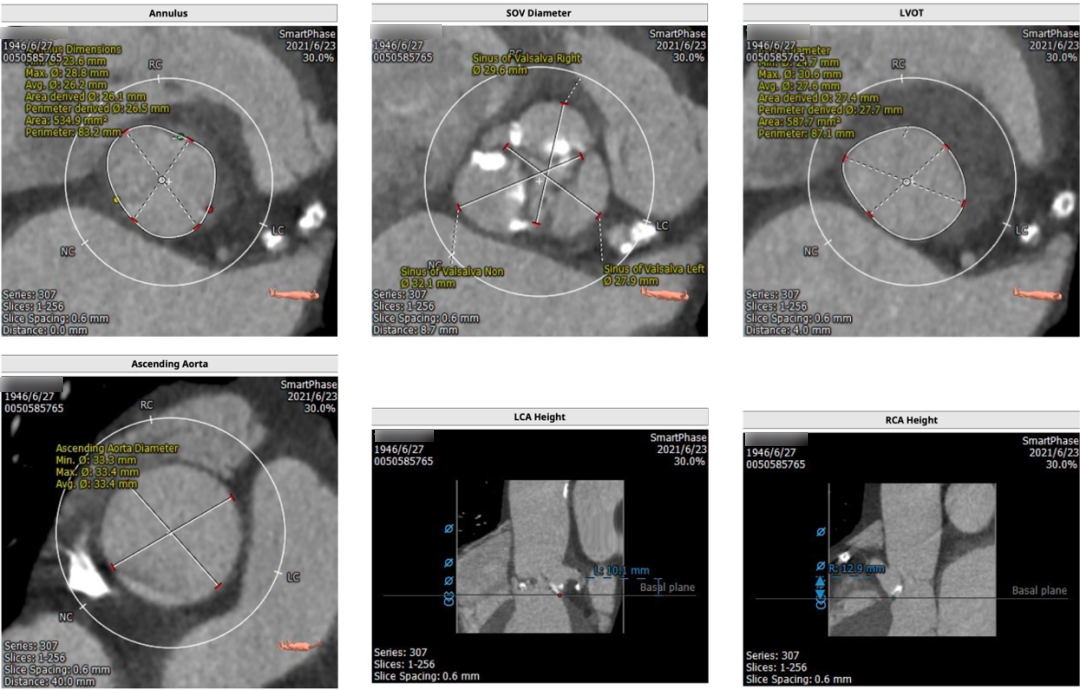

术前CT

CT提示为该患者三叶瓣,右无轻度融合,冠脉开口高度尚可,窦部空间可,髂总动脉近环形钙化,内径可,计划予以23mm球囊扩张,植入Venus A 26瓣膜。